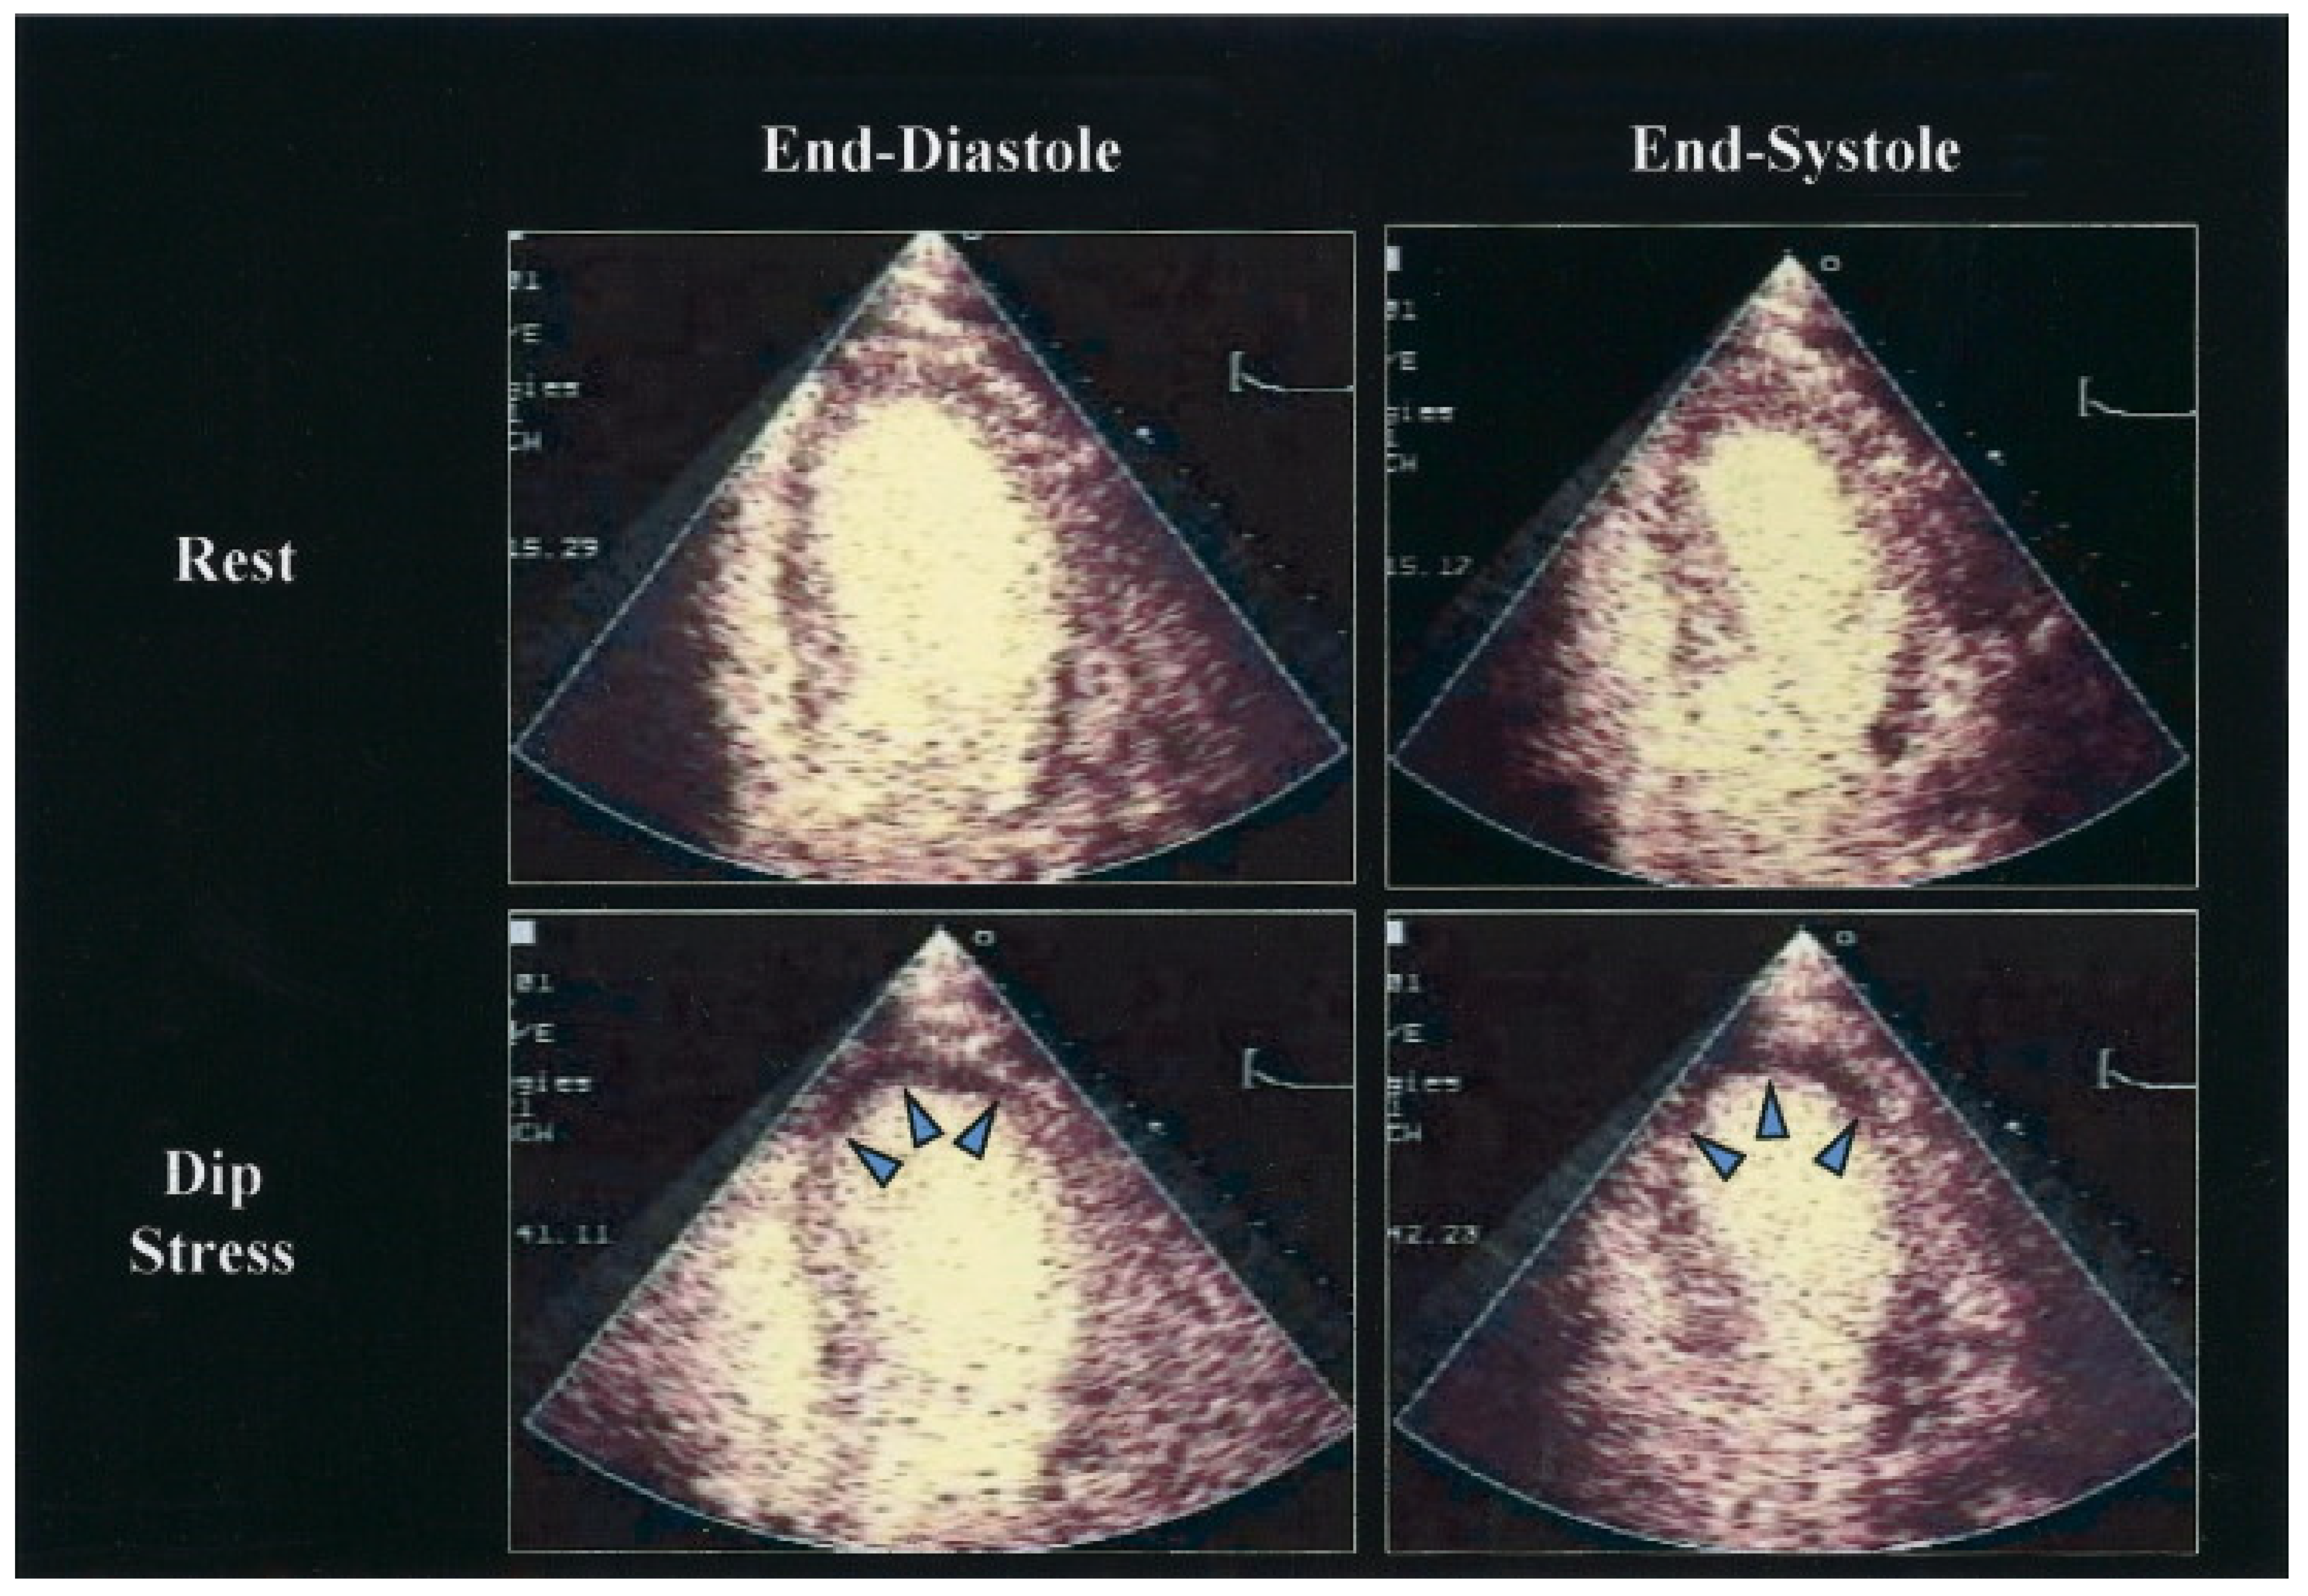

| Stress Echocardiography | − | + Hypokinesis detection (usually with dobutamine) perfusion evaluation (with contrast agent) coronary flow reserve (usually with adenosine) | Viability assessment |